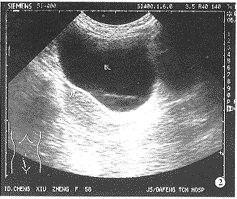

经直肠超声引导精囊穿刺注药治疗精囊炎